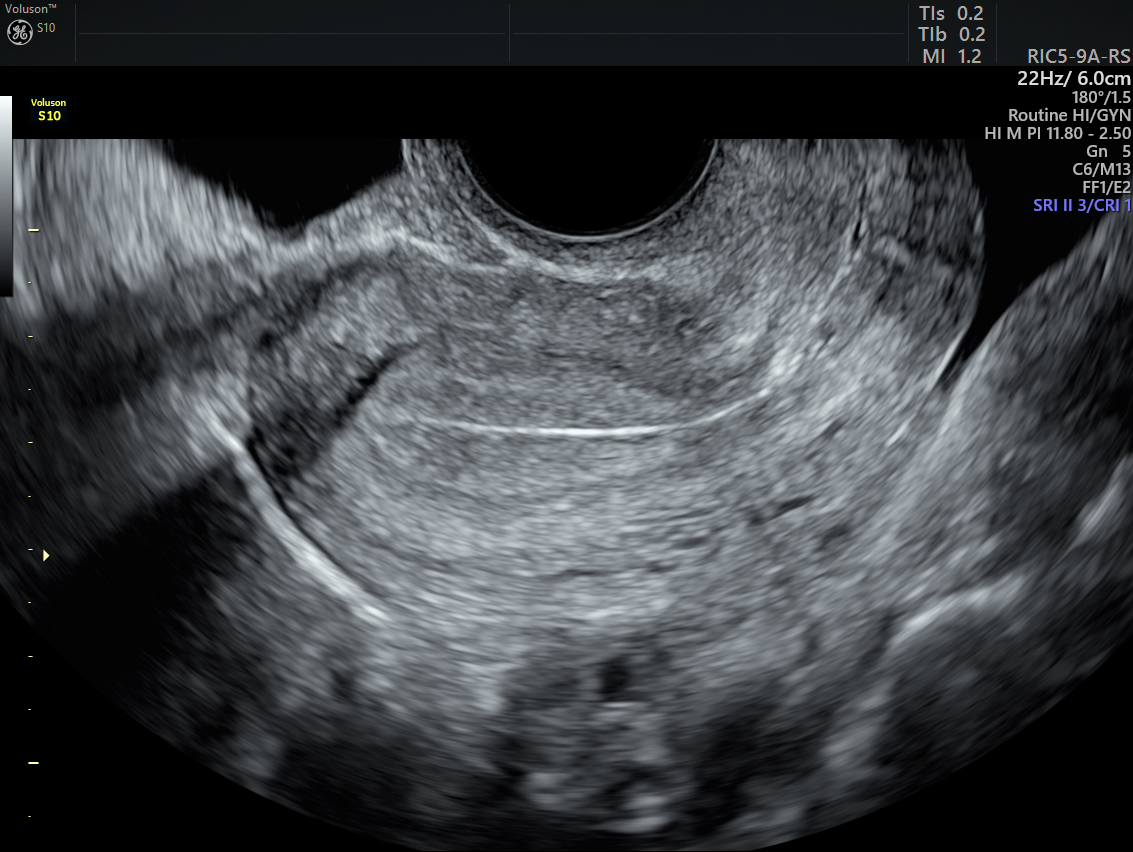

Transvaginal ultrasound showing a thick endometrial cavity with Menopause Ultrasound Diagnosis Your doctor takes many things into consideration,. How ultrasound helps perimenopausal patients. Both early menopause and primary ovarian insufficiency have been associated with an excess risk of cardiovascular disease, bone. The etiologies and evaluation of postmenopausal patients with uterine bleeding, as well as patients near the end of the. This committee opinion describes the use of transvaginal ultrasonography for the. Menopause Ultrasound Diagnosis.

From www.volusonclub.net

Postmenopausal Bleeding Treatment The Power of Ultrasound Empowered Menopause Ultrasound Diagnosis Your doctor takes many things into consideration,. Both early menopause and primary ovarian insufficiency have been associated with an excess risk of cardiovascular disease, bone. The etiologies and evaluation of postmenopausal patients with uterine bleeding, as well as patients near the end of the. The most common and first line used imaging modality for evaluating the endometrium is pelvic ultrasound. Menopause Ultrasound Diagnosis.